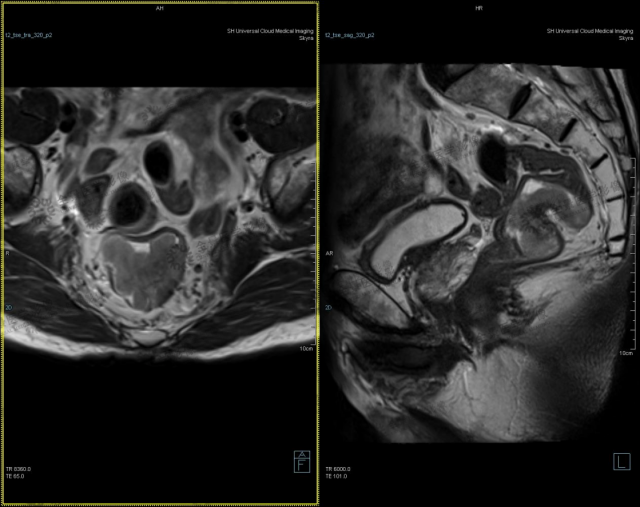

病例 3 男性,70 岁,血便 4 月余,2020-4-24 肠镜:距肛门 10 cm 肿物,病理:直肠腺癌。

直肠癌 T2 期,小视野 T2WI 可见肿块位于直肠后侧壁,侵犯肌层,但肌层低信号带连续性尚存。